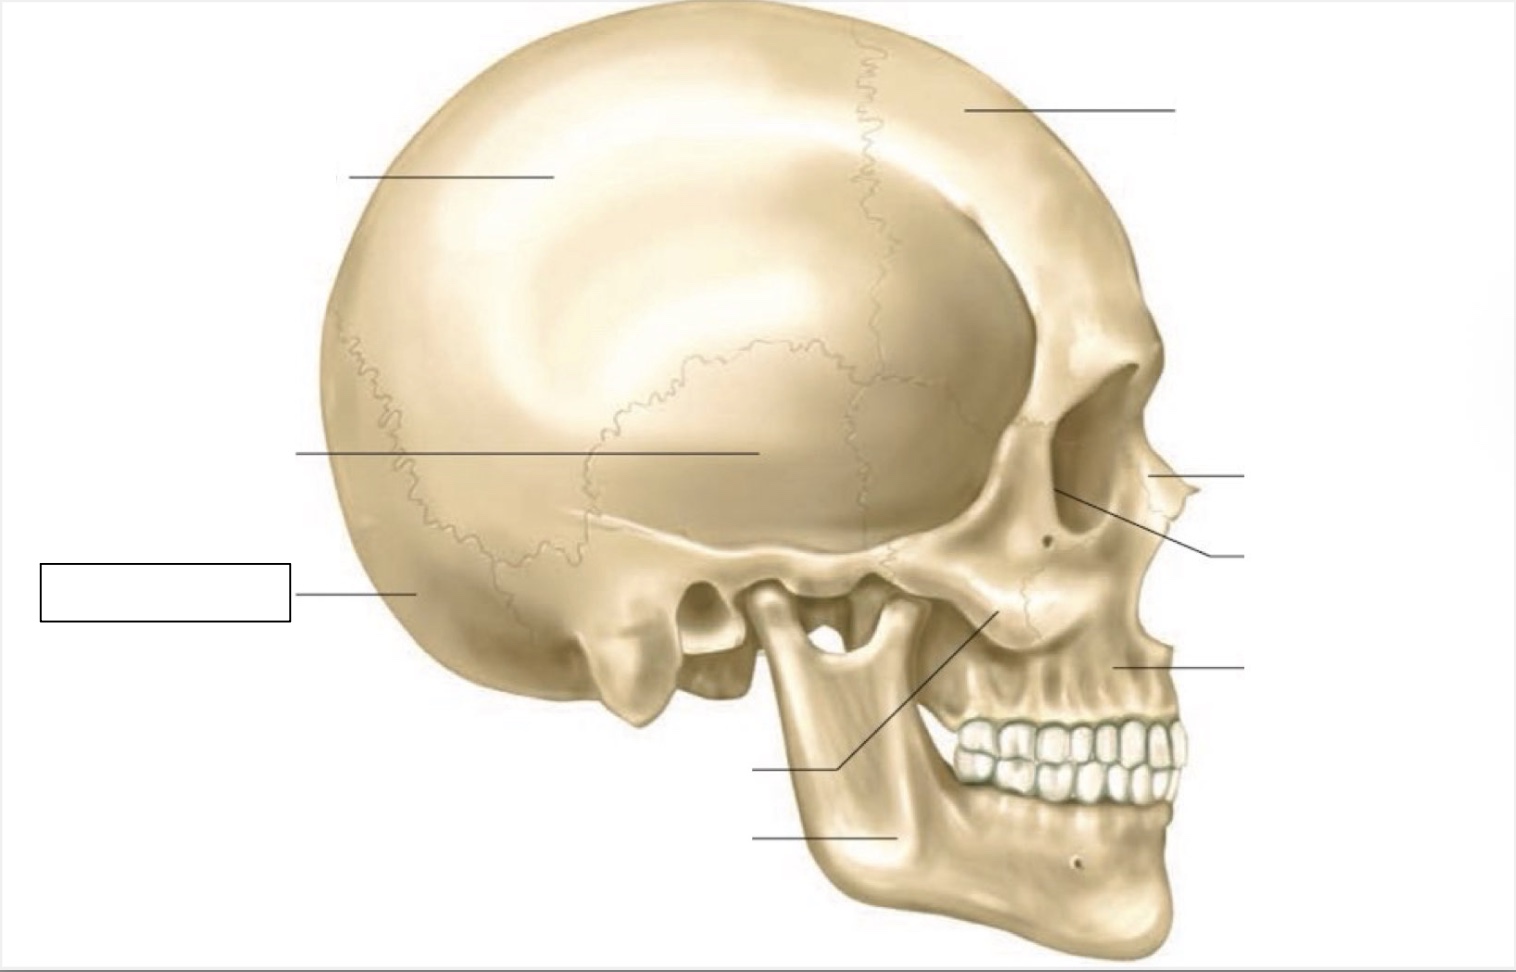

skull

frontal bone

nasal bone

orbit

maxilla

mandible

zygomatic bone

occipital bone

temporal bone

parietal bone